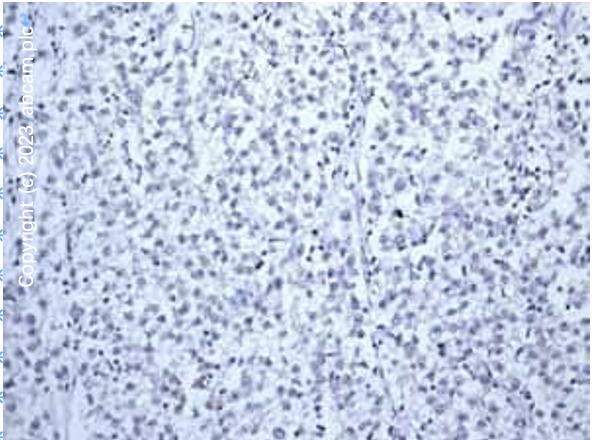

最近小编的师妹在用IHC-P的方法检测小鼠肾脏组织中的Ki67蛋白,但是她把所有的实验操作步骤和试剂都优化后还是检测不到信号,直接给小编发来一张图(图2)。

图3 IHC-P,小鼠肾脏组织,ab16667(重组Anti-Ki67抗体[SP6])。

小编分析发现,师妹的实验操作和试剂都没问题,查文献发现Ki67蛋白是一个很有特点的蛋白,主要在增殖细胞表达(蛋白水平);通常在细胞分裂的G1晚期、S期、G2期和M期表达,而在G0期不能检测到Ki67蛋白。师妹用的组织是肾脏组织,处于有丝分裂时期的细胞数目非常非常的少,所以如果不多观察一些视野或者组织不同位置的切片,可能就是无信号的结果。小编还给师妹找到了abcam产品检测Ki67在小鼠肾脏组织中的图片(图3)。最终师妹通过多观察一些视野,终于找到了阳性信号。